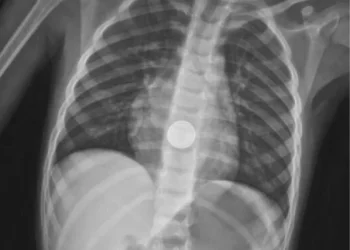

בצילום רנטגן שבוצע במיון הילדים, נצפתה הסוללה בצורה ברורה - והוזעק מיד צוות החירום של מחלקת גסטרואנטרולוגיה ילדים, בראשות ד"ר זאב דוידוביץ. בהובלתו, יחד עם המרדים ד"ר עומר רמדאן ובליווי צוות חדר הניתוח, בוצעה אנדוסקופיה דחופה תחת הרדמה כללית, שהובילה לשליפת הסוללה.